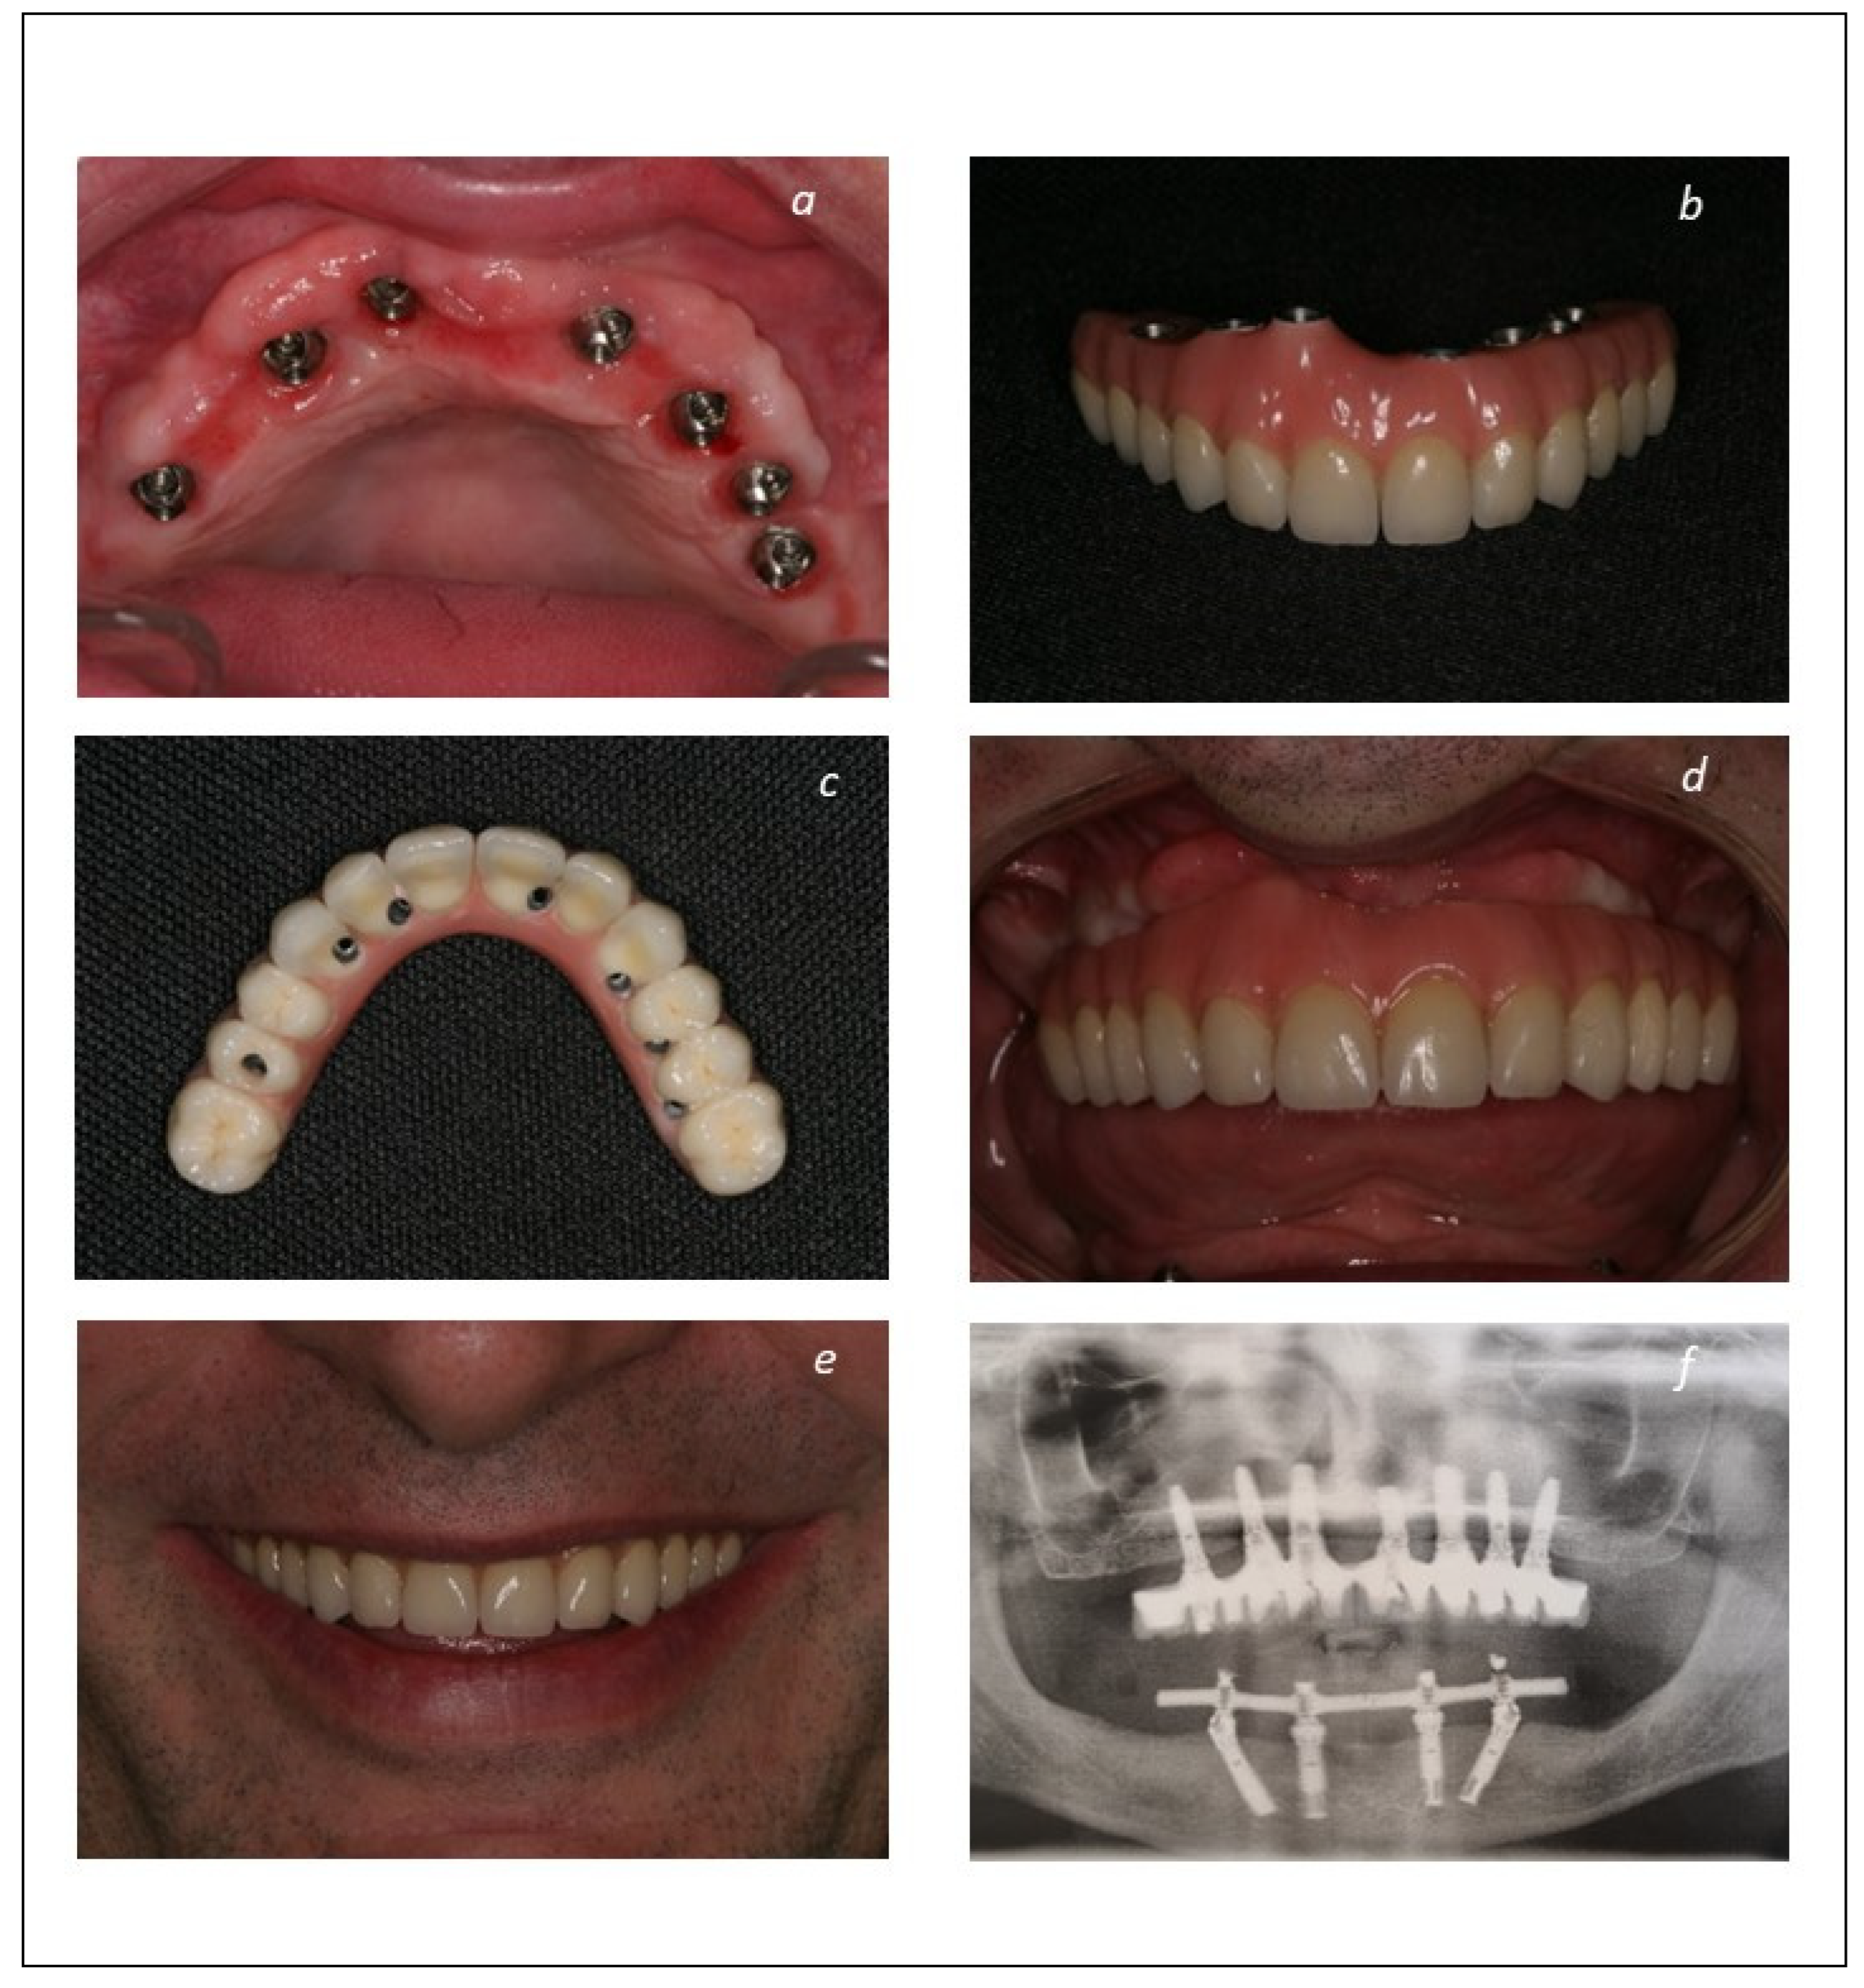

2.2. Surgical and Prosthetic Protocols